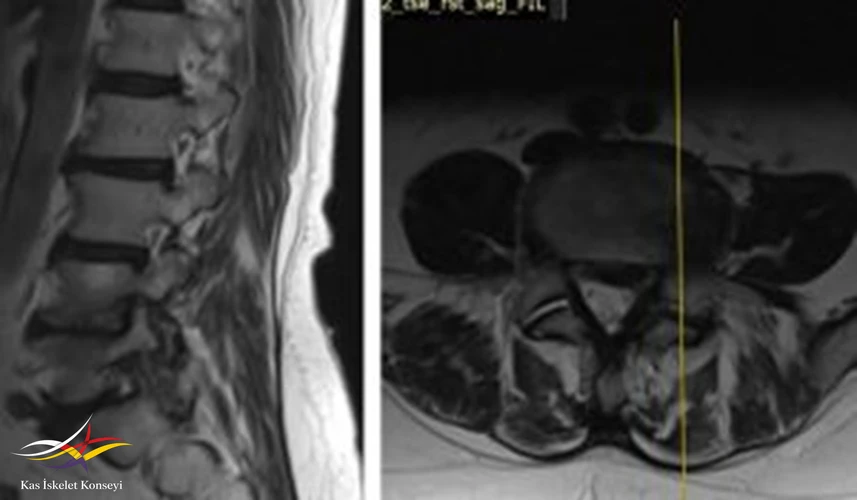

İncelemeler: Lomber MRG: L4-5 diskal bulging ve sol foraminal stenoz var. Kalça MRG istendi, iki yanlı trokanterik bursit rapor edildi.

Resim 2. Lomber MRG, L4-5 seviyesi sağ paramedian kesit.

Resim 3. Lomber MRG, L4-5 seviyesi sol paramedian kesit foramen stenozunu göstermekte.